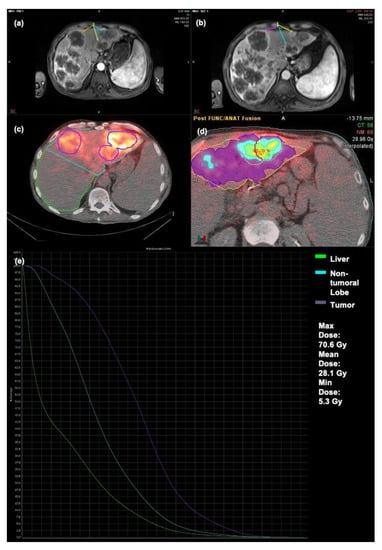

An example of a patient not showing OR can be seen in Figure 5. An amount of 20.6 mCi of resin microspheres were injected into the left hepatic artery. Subsequent MRI showed tumor progression within prior tumors increasing in size and new tumors being identified. Tumors for this patient had a mean TD of 28.1 Gy, a maximum TD of 70.6 Gy, and a minimum TD of 5.3 Gy.

Figure 5.

Patient failing to show OR following Y90 therapy (a) Pre-op MRI (b) Post-op MRI (c) Bremsstrahlung SPECT/CT (d) Dosimetry map (e) DVH Curve.